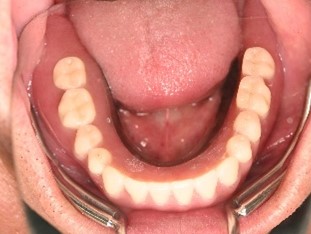

After

【義歯を装着したところ】